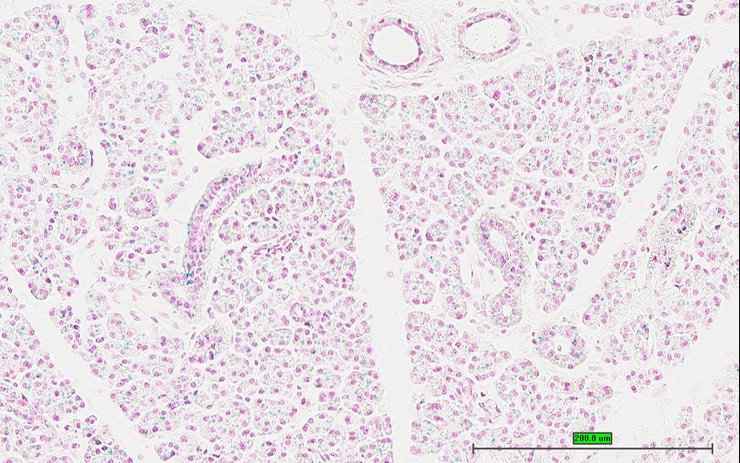

Specimen UC Davis_1873175: postnatal adult; Cox15tm1.1(KOMP)Vlcg/Cox15+ (more )

Structure Level Pattern Image Note

TS28: metanephros Present UC Davis_1873175 kidney

Specimen UC Davis_1873176: postnatal adult; Cox15tm1.1(KOMP)Vlcg/Cox15+ (more )

TS28: metanephros Present UC Davis_1873176 kidney

Specimen UC Davis_1873177: postnatal adult; Cox15tm1.1(KOMP)Vlcg/Cox15+ (more )

TS28: metanephros Present UC Davis_1873177 kidney